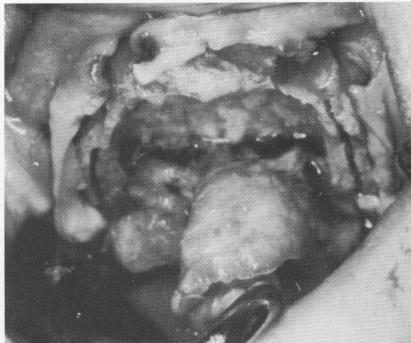

Fig. 11-177. The edentulous maxilla with recent extractions. Note the density and irregularity of the fibromucosa.

2 Edentulous maxilla with recent extractions shows irregular fibromucosa